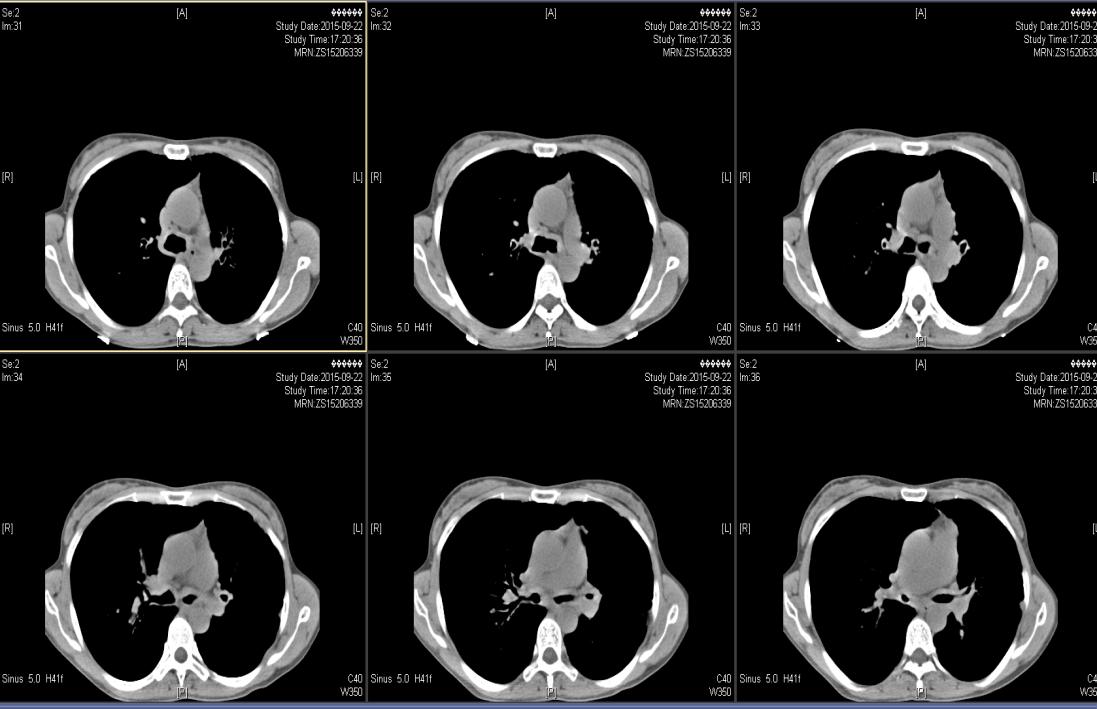

( 2015-9-22 ) 我院气管三维重建CT示 :气管、主支气管及其分支形态欠规则,管壁见明显增厚,管腔内壁凹凸欠光整,肺门处支气管管壁明显增厚,可见少许钙化,肺门处支气管管腔局部狭窄,远端分支管腔扩张呈囊柱状。见图1—图4。

图1

图2